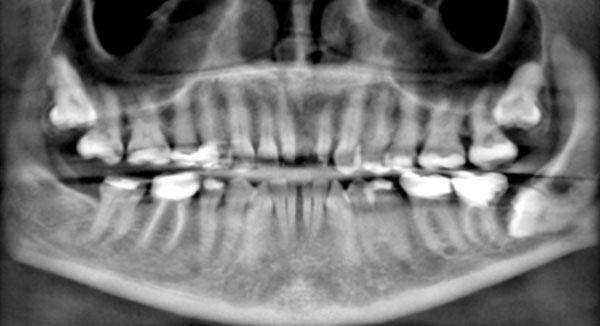

Clinical examination revealed the space formation between teeth 24 and 25 (Fig. 1a). The overlying mucosa and gingiva appeared normal in color. Deep probing elicited bleeding from the problem site. Radiographic evaluation revealed a well-circumscribed, low-density, radiolucent lesion between the mandibular central incisors, with spacing between teeth 24 and 25 (Fig. 1b) as well as thinning and expansion of the buccal and lingual cortical plates (Figs. 1c-1e). No other pathology was detected by the oral and maxillofacial radiologist on the images.

Fig. (1c).

Reconstructed panoramic radiograph shows impacted teeth, missing teeth, and migration of teeth. The mandibular left third molar is horizontally impacted against the distal surface of the second molar. The root of the molar appears to be irregular, potentially suggesting root resorption.